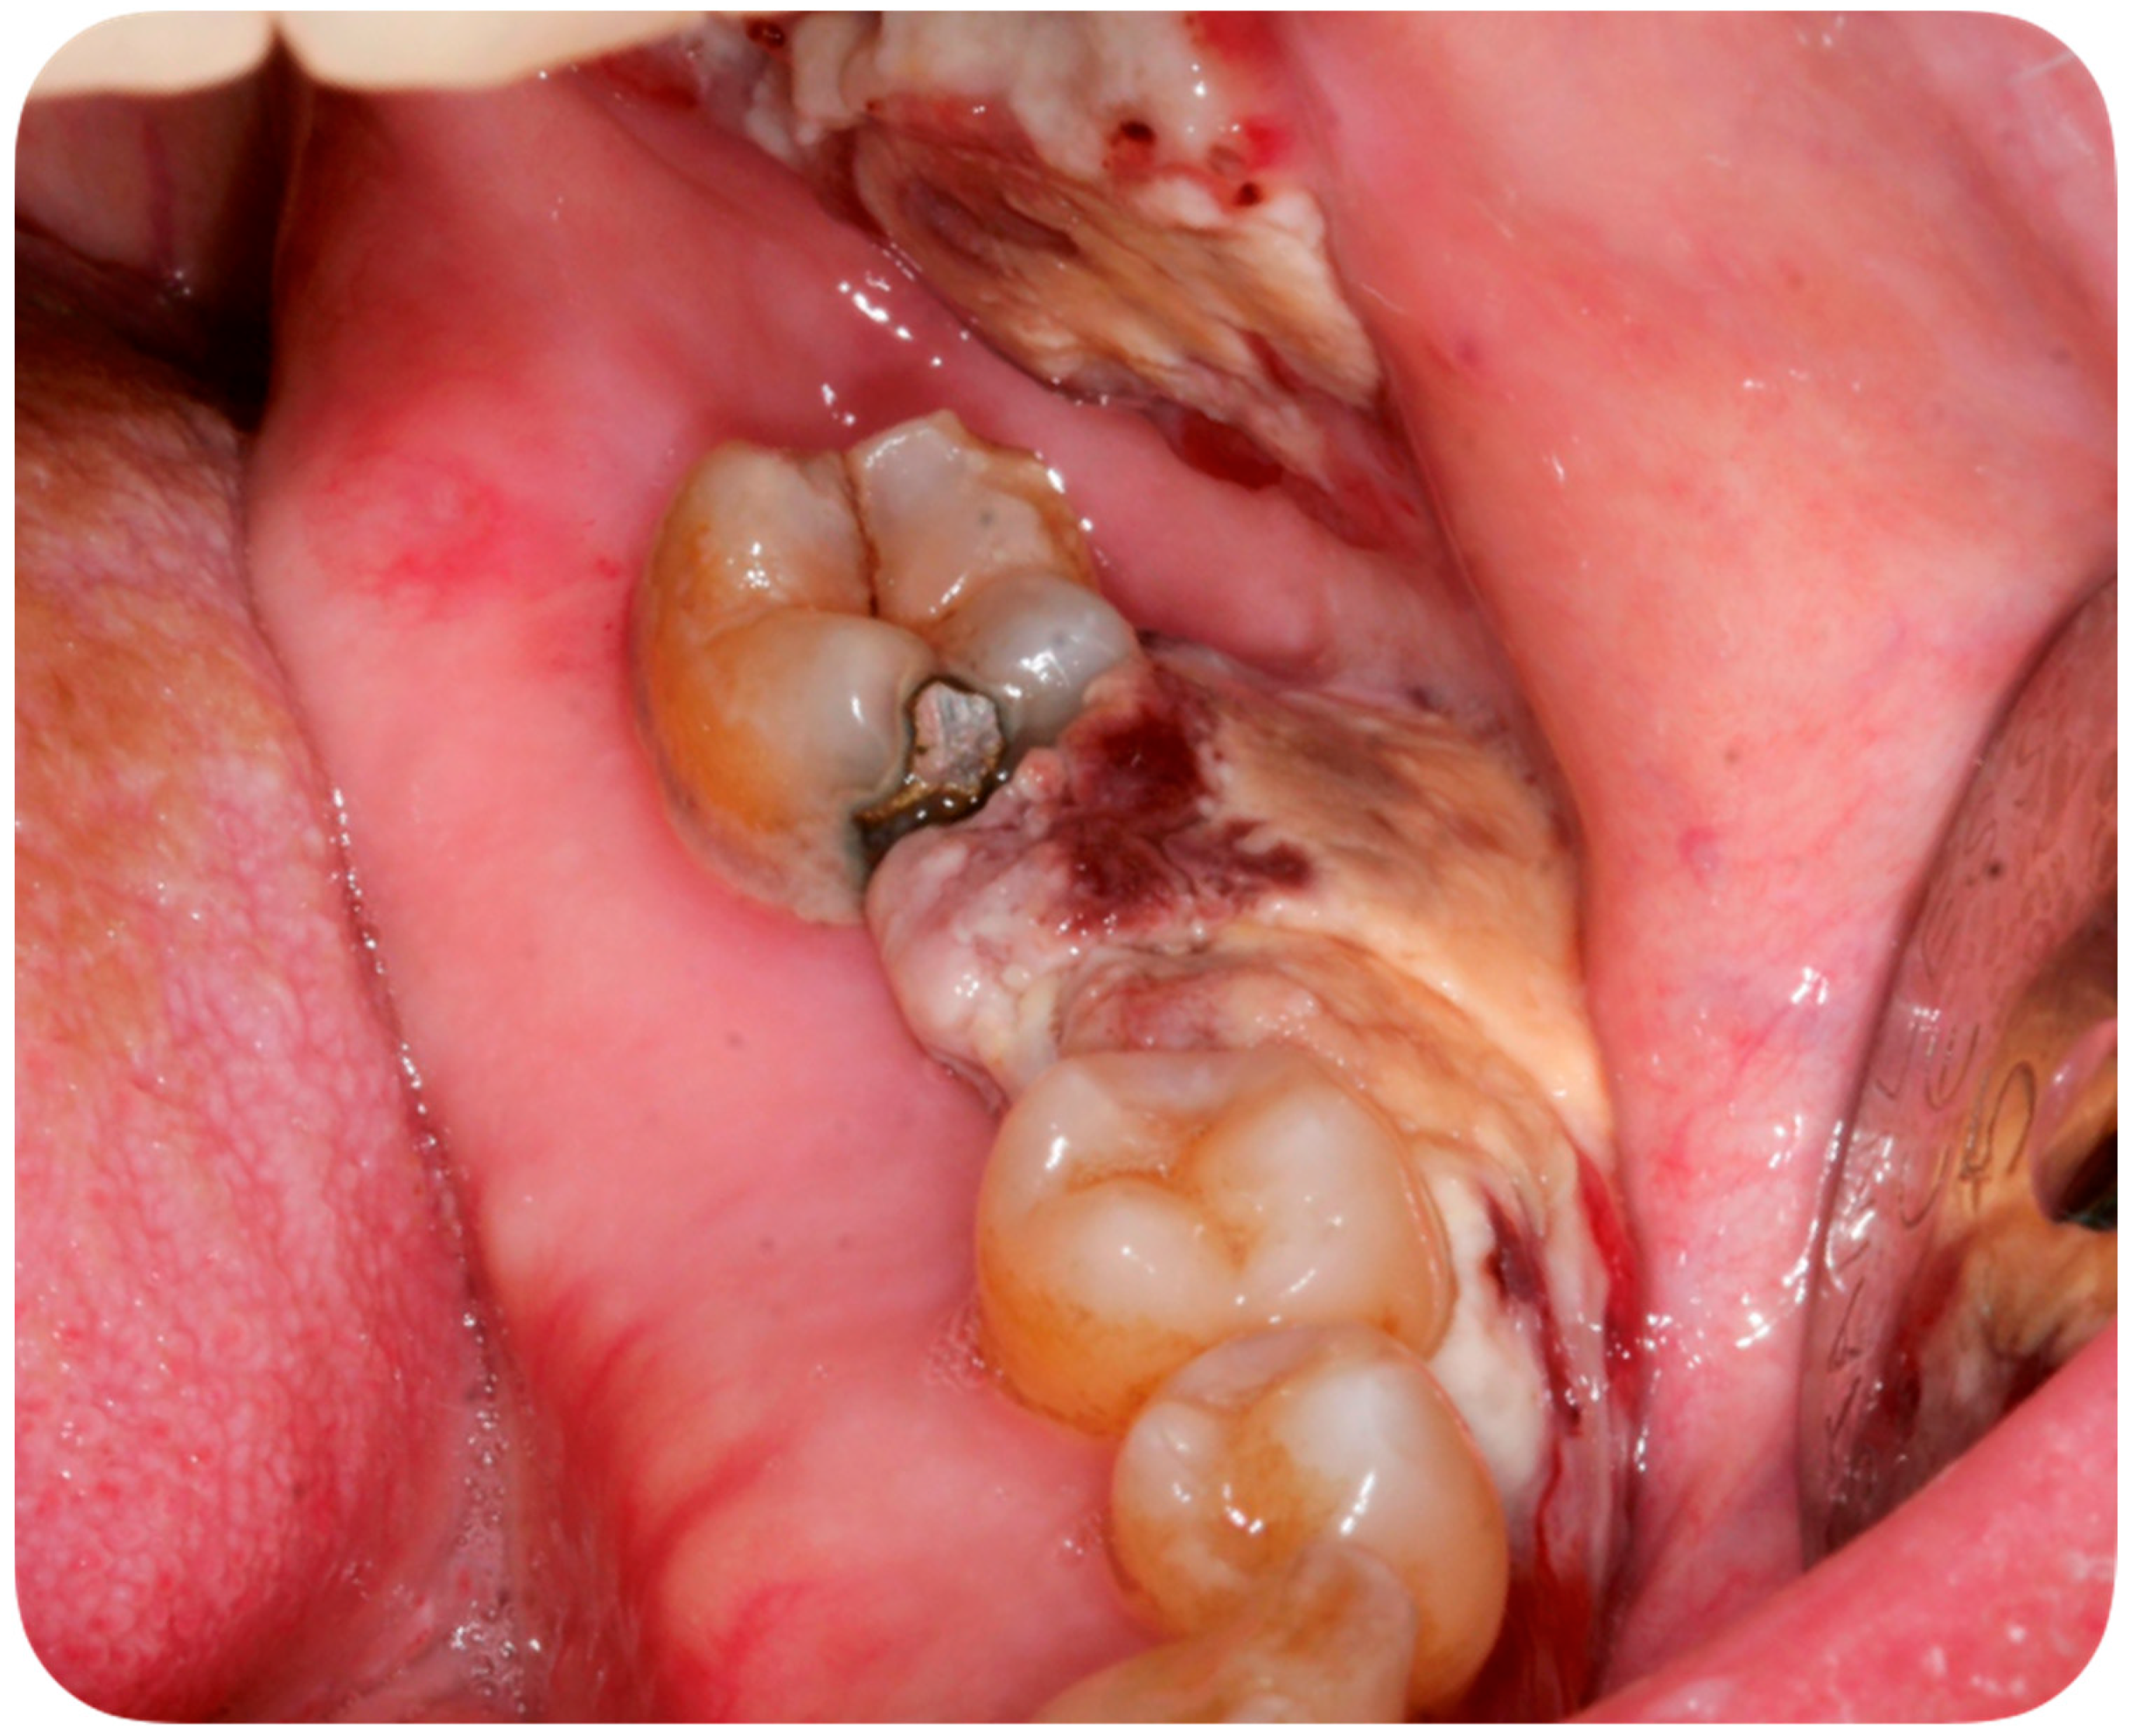

A 56-year-old Caucasian man affected by acute myeloid leukemia (AML) was admitted to the Hematological Department of Policlinico A. Gemelli (Rome, Italy) for febrile neutropenia with multiple oral swellings. The patient’s medical history revealed previous diagnoses of myelodysplastic syndrome (2016), refractory anemia with excess blasts type 1 (RAEB-1), which was treated with ten cycles of decitabine and an allogenic hematopoietic stem cell transplantation. This recurring disease evolved into Acute Myeloid Leukemia (2018). Consequently, re-induction chemotherapy was administered using Chlorambucil and Cytarabine first, followed by a combination of Azacitidine and Venetoclax. In October 2019, the patient was hospitalized for febrile neutropenia with severe thrombocytopenia. At that moment, the patient was receiving antifungal prophylaxis with Posaconazole 300 mg/die. Blood culture was performed and the research for yeasts was negative. The physical examination did not retrieve any skin lesion. The oral examination revealed that three rapidly growing asymptomatic ulcerated swellings, located on both the buccal mucosa and the left mandible, arose 15 days before (Figure 2, Figure 3 and Figure 4).

Figure 4. Asymptomatic ulcerated lesion, located on the left mandible.

Lesions were light-grayish in color, friable, with a 4 cm diameter, and protruded from the mucosa, interfering with chewing. After a platelet transfusion and local anesthesia (Carbocaine 2% with epinephrine 1:100,000; Dentsply, Verona, Italy), an incisional biopsy was performed together with a microbiological sampling for fungi. The pathology revealed an inflammatory process in association with purulent necrosis and microbial colonies; no granulomas were detected in the specimen. Part of the sample was discharged in liquid Amies medium, then streak-plated on Sabouraud dextrose agar plates supplemented with gentamicin and chloramphenicol (Bio-Rad, Hercules, CA, USA) and BBL CHROMagar Candida plate (BD). We identified species using Bruker Biotyper version MBT 3.1 matrix-assisted laser desorption/ionization time-of-flight (MALDI-TOF) mass spectrometry (Bruker) and nucleotide sequence analysis of the internal transcribed spacer (ITS) regions of the rRNA gene. Microbiological sampling was thus positive for S. clavata, thus the final diagnosis indicated an intraoral fungal infection due to S. clavata. The Minimal inhibitory concentrantions (MICs) of antifungal drugs were determined in parallel according to the European Committee on Antimicrobial Susceptibility Testing (EUCAST) standardized broth microdilution method [27].

This case report describes the first case of oral lesions as the first manifestation of S. clavata infection and the literature review did not find any other case with oral involvement, thus differential diagnosis was particularly demanding. The infection manifested as three rapidly growing asymptomatic ulcerated swellings, located on both the buccal mucosa and the left mandible, that arose 15 days before. Lesions were light grayish in color, friable, with a 4 cm diameter, and protruded from the mucosa, interfering with chewing (Figure 1). Since clinical presentation of common and rare diseases can be really unusual in immunosuppressed patients, the diagnosis of these lesions was particularly challenging, but some clinical characteristics drove the differential diagnosis: rapid growth, ulcerating feature, bilateral onset, and absence of any other symptom (i.e., pain, itching, burning sensation). For these reasons, oral or deep fungal infections, other opportunistic infections, relapses, or new onset of hematological diseases and granulomatous diseases have been considered in the differential diagnosis (Table 3).